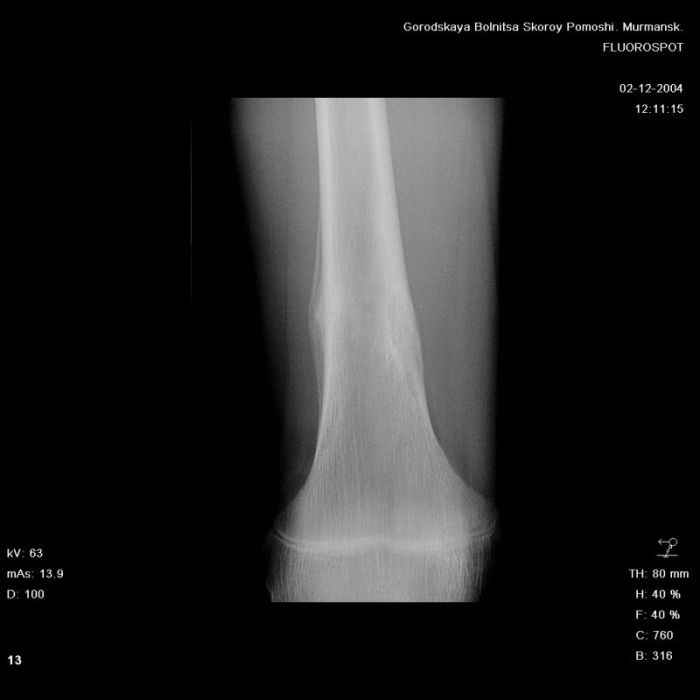

Анамнез практически никакой: в следствие травмы (растяжение связок коленного сустава) от 07.11.2004 выполнены Rg-граммы в травмпункте и обнаружено опухолевидное образование. Первичные Rg-граммы я не публикую, так как они заметно худшего качества, да и динамики за прошедшие три недели не отражают. Болевой синдром купирован в течение трёх дней. В настоящий момент мальчика ничего не беспокоит. Ходьба не нарушена, опухоль пальпируется с трудом по задней поверхности в н\3 правого бедра, пальпация безболезненна, объем движений в суставах правой нижней конечности полный и симметричный. Кожа над опухолью не изменена.В нашей клинике проведено дополнительное обследование: общие анализы крови и мочи, биохимия крови без особенностей. Выполнены Rg-граммы на цифровом Siemens обычные и продольные томограммы срезами 3-5 мм, а также компьютерная томография поперечными срезами по 5 мм. Прошу обратить внимание, что на приведённых томограммах видны две полости 10х15 мм и 15х60 мм. Также имеются два опухолевидных образований наслаивающихся друг на друга: уплощённое и вытянутое 10х100 мм и элипсовидной формы 15х30 мм. Это хорошо заметно на фото a_1.jpg c_1.jpg и d_1.jpg. Плотность внутри полостей 125% от плотности костномозгового канала, плотность наружного опухолевидного образования 55% от плотности кортикального слоя. Также отмечается линия перелома по центру наружного опухолевидного образования.Исходя из полученных данных мнения в плане диагноза несколько разделились от 1)сочетания кортикальной фиброзной дисплазии и латентно протекавшего маршевого перелома н\3 правого бедра до 2)остеосаркомы. В отношении первого варианта не сходится отсутствие клиники при переломе такой крупной кости как бедро, второй вариант вообще оставлю без комментария, ибо некомпетентен. Хотелось бы услышать мнения коллег, с удовольствием ознакомлюсь с любыми предположениями и замечаниями.С уважением, Александр Е. КлоковОтделение детской ортопедии и травматологииБСМП г. Мурманска.